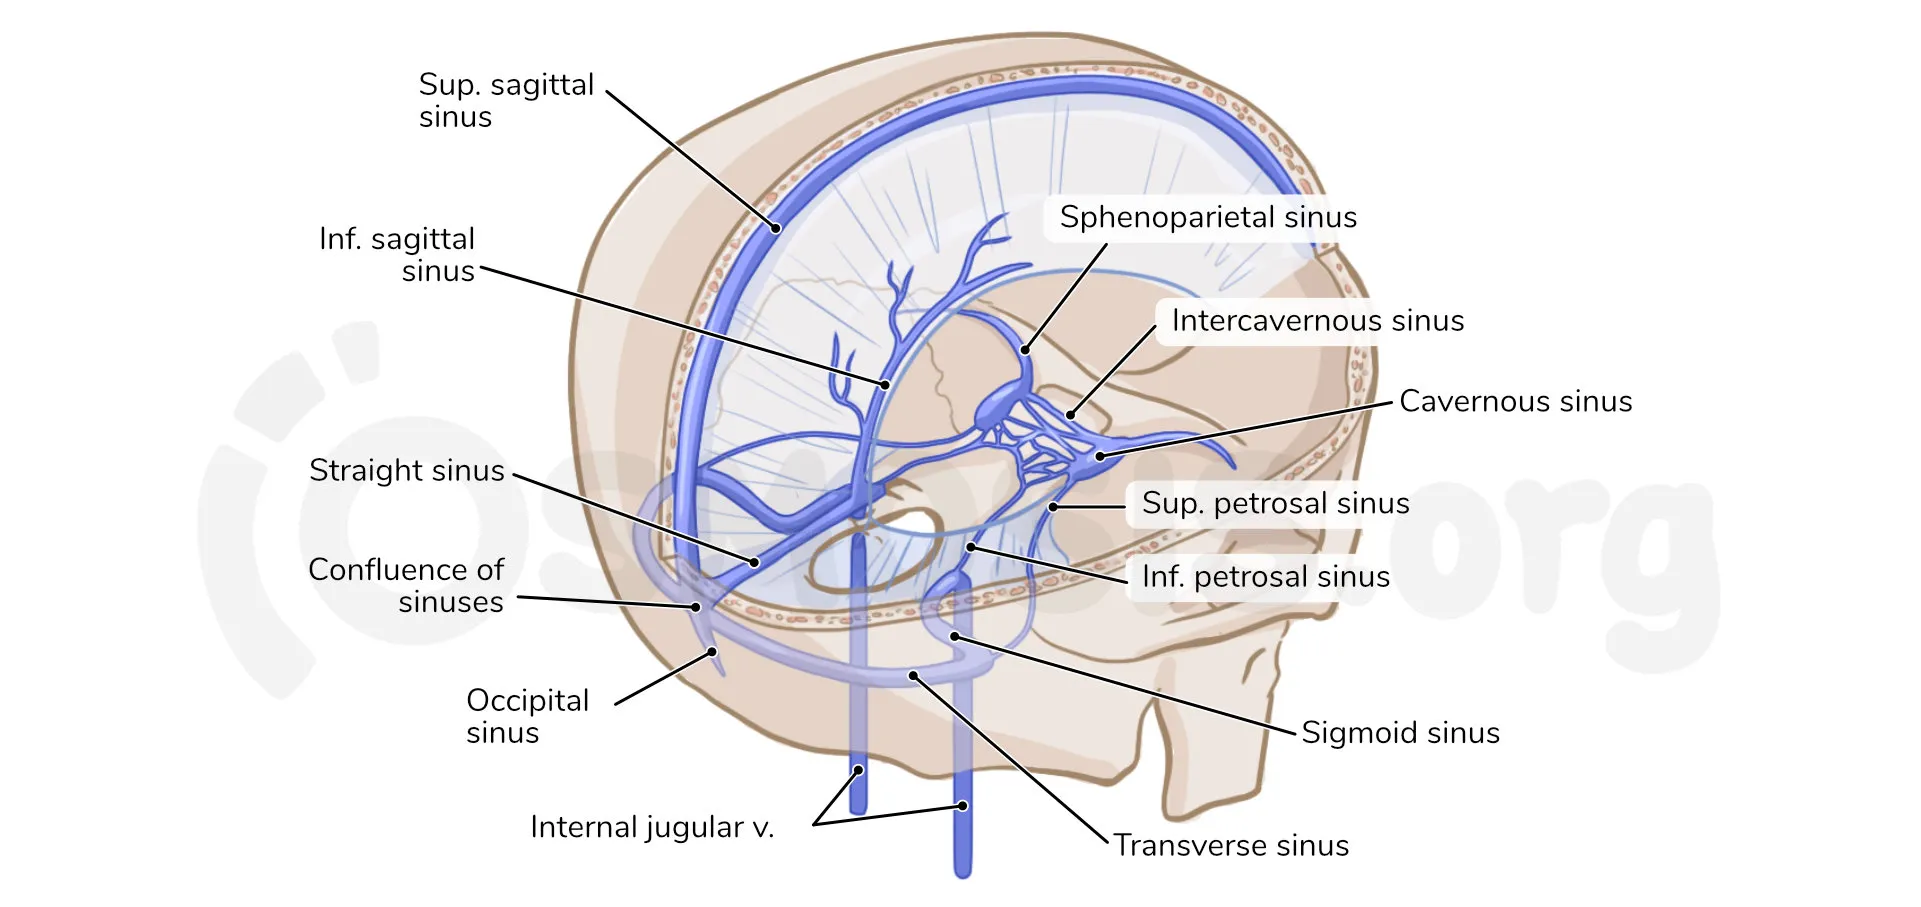

Superior sagittal sinus

Straight sinus

Confluence of sinuses

Transverse sinuses

Sigmoid sinuses

Cavernous sinuses

Intercavernous sinus

Superior petrosal sinuses/inferior petrosal sinuses

Occipital sinus

Sphenoparietal sinuses